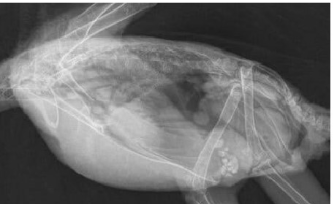

What species is this thorax and what can we note about it?

ferret

longer thorax and heart is very caudal and close do the diaphragm